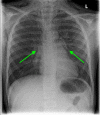

Tracheal lacerations in the paediatric population are not common; however, they can be life-threatening. Prompt diagnosis and management are essential for a good prognosis. Here, we present the case of a nine-year-old boy who presented to the hospital following a bicycle handlebar injury with neck pain and subcutaneous emphysema of the anterior thorax and neck. Chest X-ray revealed pneumomediastinum and a small pneumothorax. A computed tomography scan revealed a posterior longitudinal laceration of the trachea, measuring 1.5 cm, located superior to the carina at T1/2. As the patient was clinically stable, did not require any supplemental oxygen, and the tear was smaller than 2 cm, conservative management with steroids and broad-spectrum antibiotics was implemented. The patient was transferred to a tertiary ENT centre in Glasgow for observation in the paediatric intensive care unit where he recovered uneventfully. A repeat cross-sectional imaging six days after the injury revealed successful healing of the laceration. Non-surgical management of a tracheobronchial injury can be an effective approach. This can be considered in the case of tears measuring <2 cm and in clinically stable patients. Imaging-based diagnosis in the case of patients with minor injuries who are improving with conservative treatment may be sufficient, and confirmation with bronchoscopy would be of questionable clinical value in such patients.